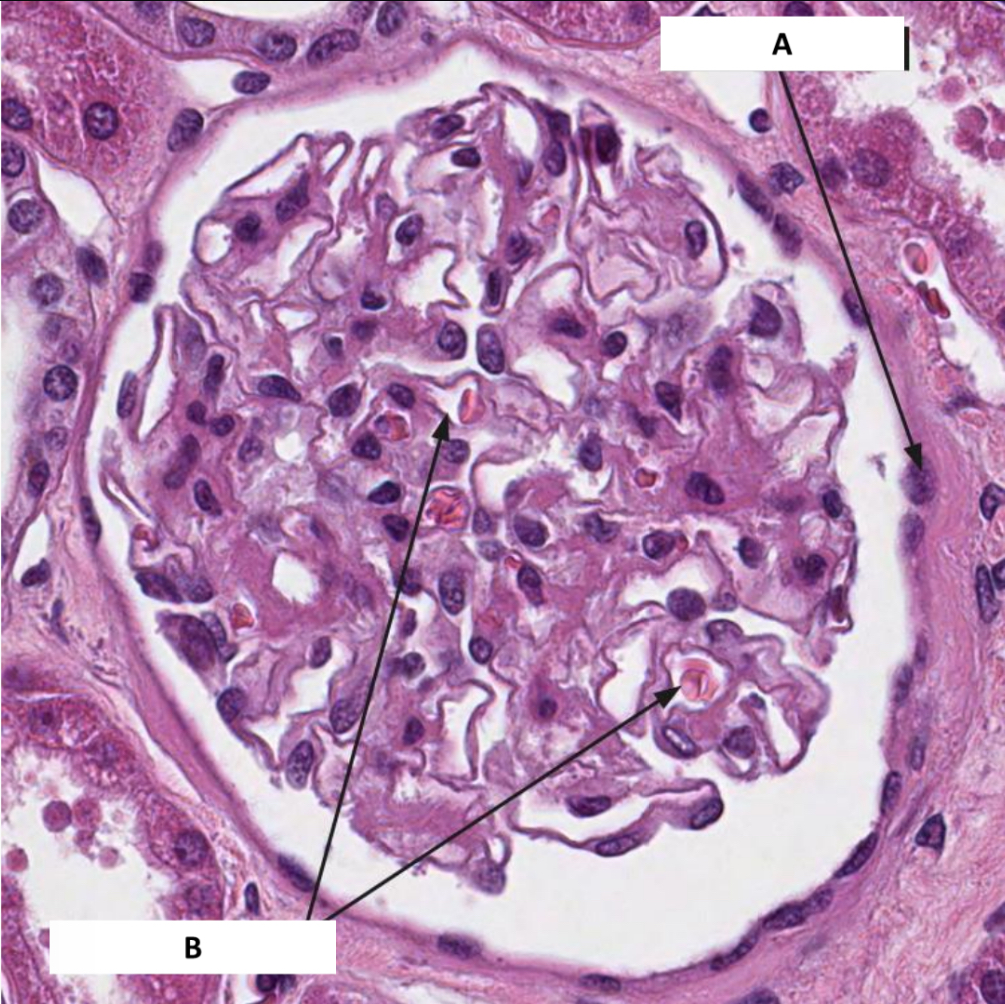

Name the structure indicated by A.

Bowman’s capsule

Name the structure indicated by B.

Capillary loops

Name the structure indicated by 1.

Parietal layer of capsule

Name the structure indicated by 2.

Capsular space

Name the structure indicated by 3.

Visceral layer of capsule (podocytes)

Name the structure indicated by 4.

Capillary